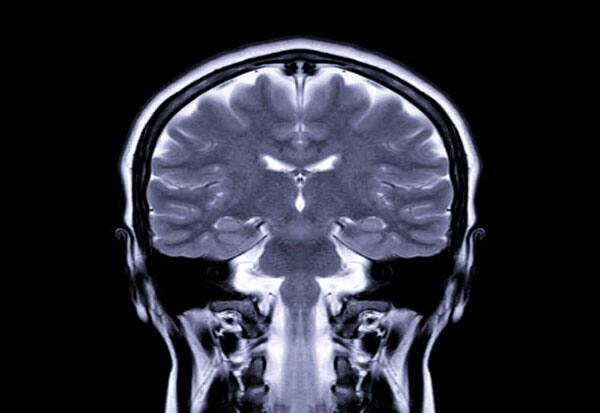

Researchers followed 91 teenagers for seven years. Mental processes involved in cognitive control were analysed using fMRI brain scans, taken as the participants performed the Multi-Source Interference Task (MSIT).

The task is known to trigger activity in the brain's dorsal anterior cingulate cortex (dACC) -- crucial for cognitive control and attention while performing tasks involving distractions. The participants had never taken substances at the start of the study.